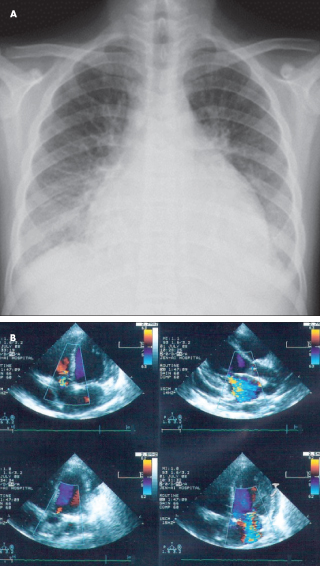

<p><span><strong><br>ABSTRACT:</strong></span> Children with acute myocarditis often present with dyspnea at rest, exercise intolerance, syncope, tachypnea,...